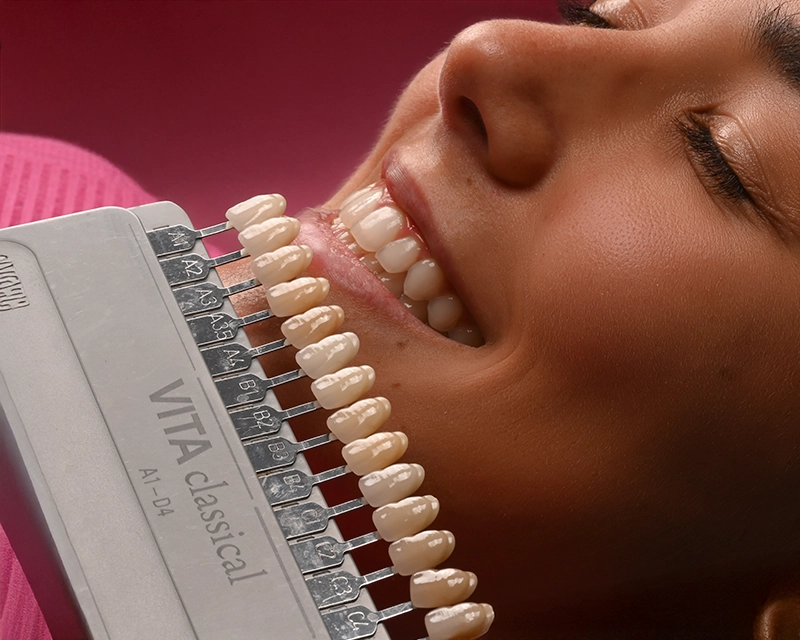

Le faccette sono sottilissime lamine di porcellana (fini come una lente a contatto), che si applicano sulla superficie esterna dei denti per modificarne:

- Forma

- Colore

- Dimensione

- Eventuali imperfezioni

Il risultato? Un sorriso perfetto, naturale e personalizzato.

Le faccette sono sottilissime lamine di porcellana (fini come una lente a contatto), che si applicano sulla superficie esterna dei denti per modificarne:

- Forma

- Colore

- Dimensione

- Eventuali imperfezioni

Foto del viso e della bocca, impronte dei denti e creazione del mock-up (una simulazione in 3D delle tue faccette dentali).